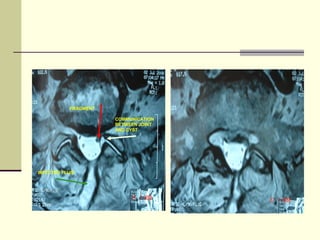

FRAGMENT

COMMUNICATION

BETWEEN JOINT

AND CYST

INFECTED FLUID

DIFFRENTIAL DIAGNOSIS